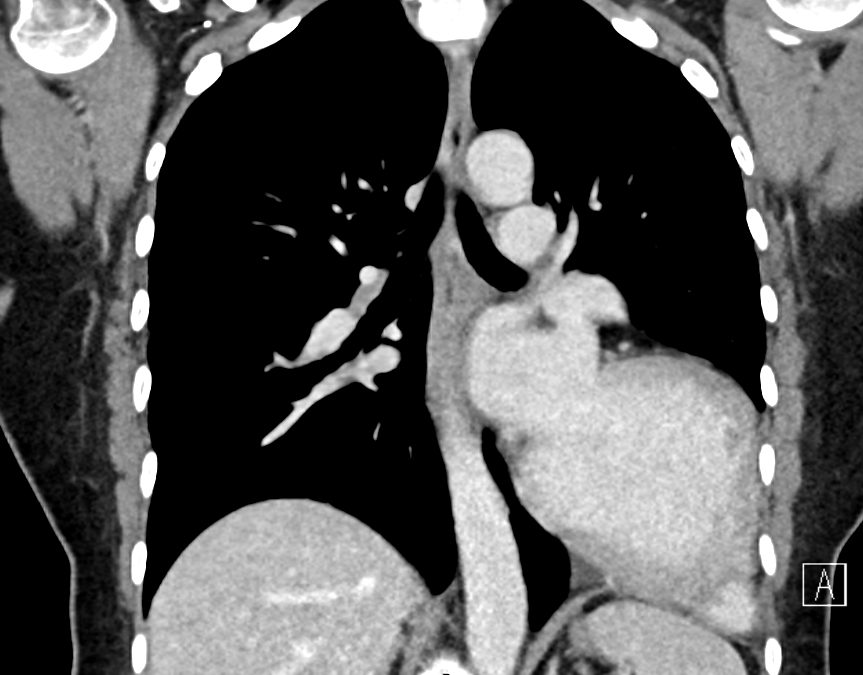

Conclusion: Pericardial agenesis should be suspected in patients with marked levoposition of the cardiac silhouette, loss of right heart border, prominent pulmonary artery and lung tissue interposing between main pulmonary artery and aorta as well as between the heart and spine. The main complications are herniation and compression of the left coronary artery.

Fig 3: CT: displacement of the heart with the trachea remaining in the middle, and interposition of the lung between the diaphragm and inferior border of the heart